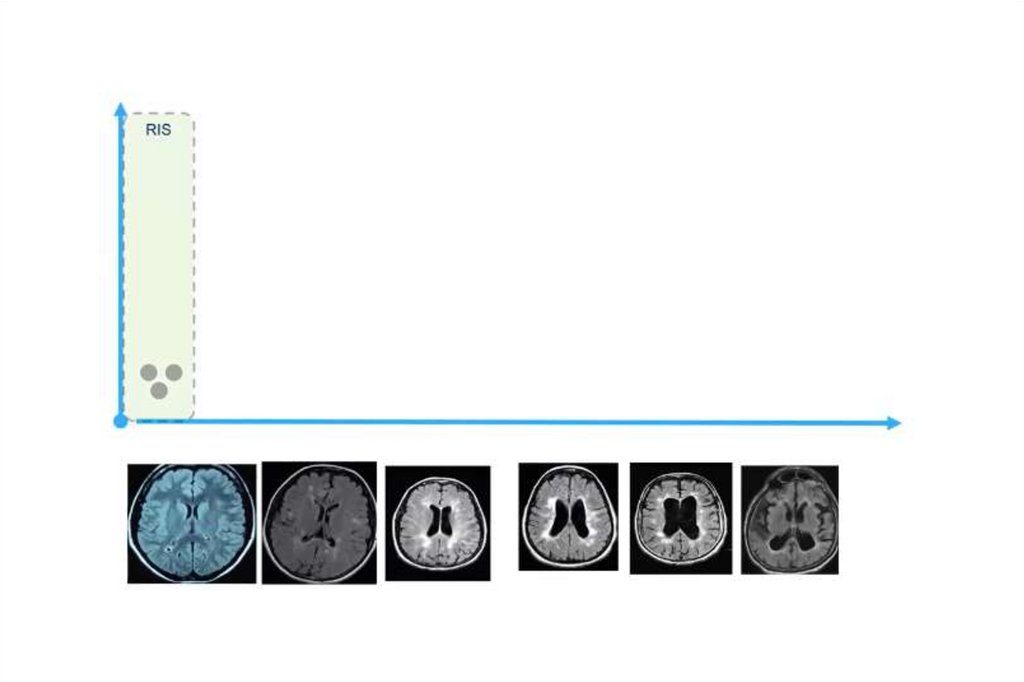

Subklinik /Asemptomatik (nonfazik) - MS

MS’lilerin asemptomatik aile fertlerinde;

• MRG’ de MS’ le uyumlu görüntü

• BOS’ ta OCB (+)

• VEP’ de ileti uzaması

Tanısı konmuş her bir MS’li için tanısı

konmamış bir veya iki MS’li var !